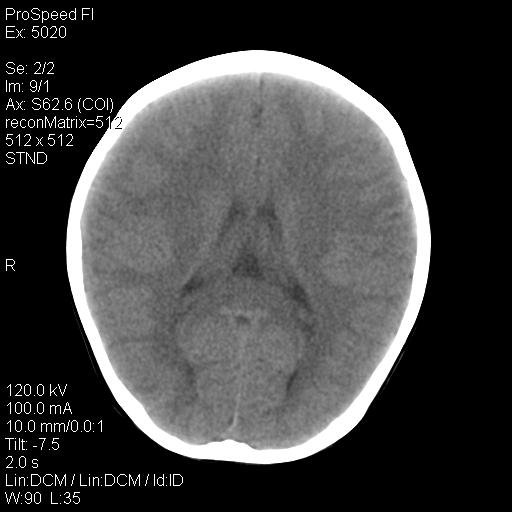

标题: PED1637:M 6Y 顶部无痛性包块两月。 [打印本页]

标题: PED1637:M 6Y 顶部无痛性包块两月。

2、颅骨局部缺失,边缘光滑、整齐

颅骨的病损表现为内外颅骨板层不规则的锋利的破坏,形成“斜边缘”,有一定的特点

颅骨为好发部位,生长缓慢,常位于顶骨、枕骨及颞骨,表现为颅骨缺损,呈圆形或椭圆形,边界清,无硬化

事发冠状缝与矢状缝交界区,密度较低,考虑表皮样囊肿可能性大,其次不除外嗜酸性肉芽肿